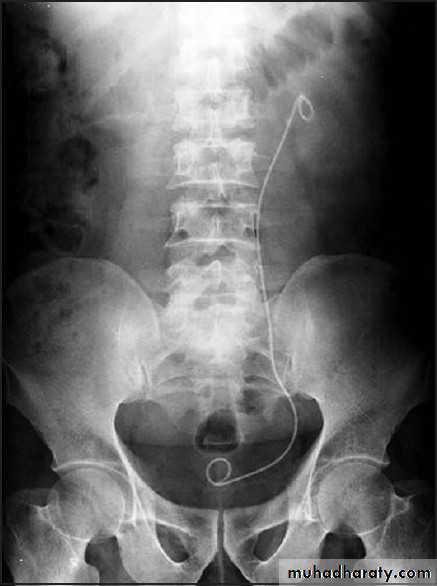

URETERAL STENTS

• Ureteral stents are a mainstay in the urological armamentarium.

• utilized in:

• treatment of urolithiasis including postureteroscopy

• preshockwave lithotripsy

• to relieve symptomatic renal colic

• to provide urinary drainage in nongenitourinary causes of ureteral obstruction, such as pregnancy and malignant ureteral obstruction

• To serve as a surgical landmark for ureteral identification in order to avoid iatrogenic ureteral injury in abdominal or pelvic surgery.

• Ureteral stents decrease the frequency and amplitude of ureteral contractions.

• The ureter and ureteral orifice are theorized to passively dilate from the stent, thus facilitating drainage.

• Available in various sizes, designs & materials.